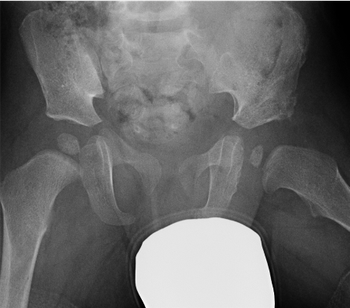

Developmental dysplasia of the hip (DDH) is a dislocation of the hip joint that is present at birth. The condition is found in babies or young children. A hip that is truly dislocated in an infant should be detected at birth, but some cases are mild and symptoms may not develop until after birth, which is why multiple exams are recommended.